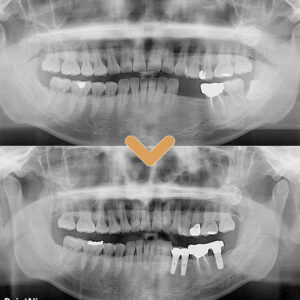

수암동치과 적절한 시기에 식립을

수암동치과 적절한 시기에 식립을 임플란트 치료는 자연치아를 대체할 수 있는 효과적인 방법으로 널리 알려져 있지만, 많은 분들이 ‘언제 임플란트를 해야 하는지’에 대해 혼란을 느끼는 경우가 많습니다. ​ 치아를 뽑고 나서 바로 해야 할지, 아니면 시간이 지나고 해도 괜찮은지에 대한 궁금증은 더보기…